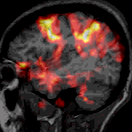

Using brain scanning, and the comparison of the two versions of the film, Naci and colleagues were able to show that the unscrambled, suspenseful version activated nearly every part of the cortex. Everything from primary sensory areas, to motor areas, to areas involved in memory and anticipation were engaged (as you might hope from a film from one of the masters of storytelling). The researchers were particularly interested in a network of activity that rose and fell in synchrony across ‘executive’ areas of the brain – those known to be involved in planning, anticipation, and integrating information from different sources. This network, they found, responded to the moments of highest suspense in the film; the moments when the boy was about to fire, for example. These were the moments you could only find so dramatic if you were following the plot.

Next the researchers showed the film to two patients in wakeful comas. In one, the auditory cortex became activated, but nothing beyond this primary sensory region. Their brain was responding to sounds, perhaps automatically, but there was no evidence of more complex processing. But in a second patient, who had been hospitalised and non-responsive for 16 years, his brain response matched those of the healthy controls who’d seen the film. Like them, activity across the cortex rose and fell with the action of the film, indicating an inner consciousness rich enough to follow the plot.